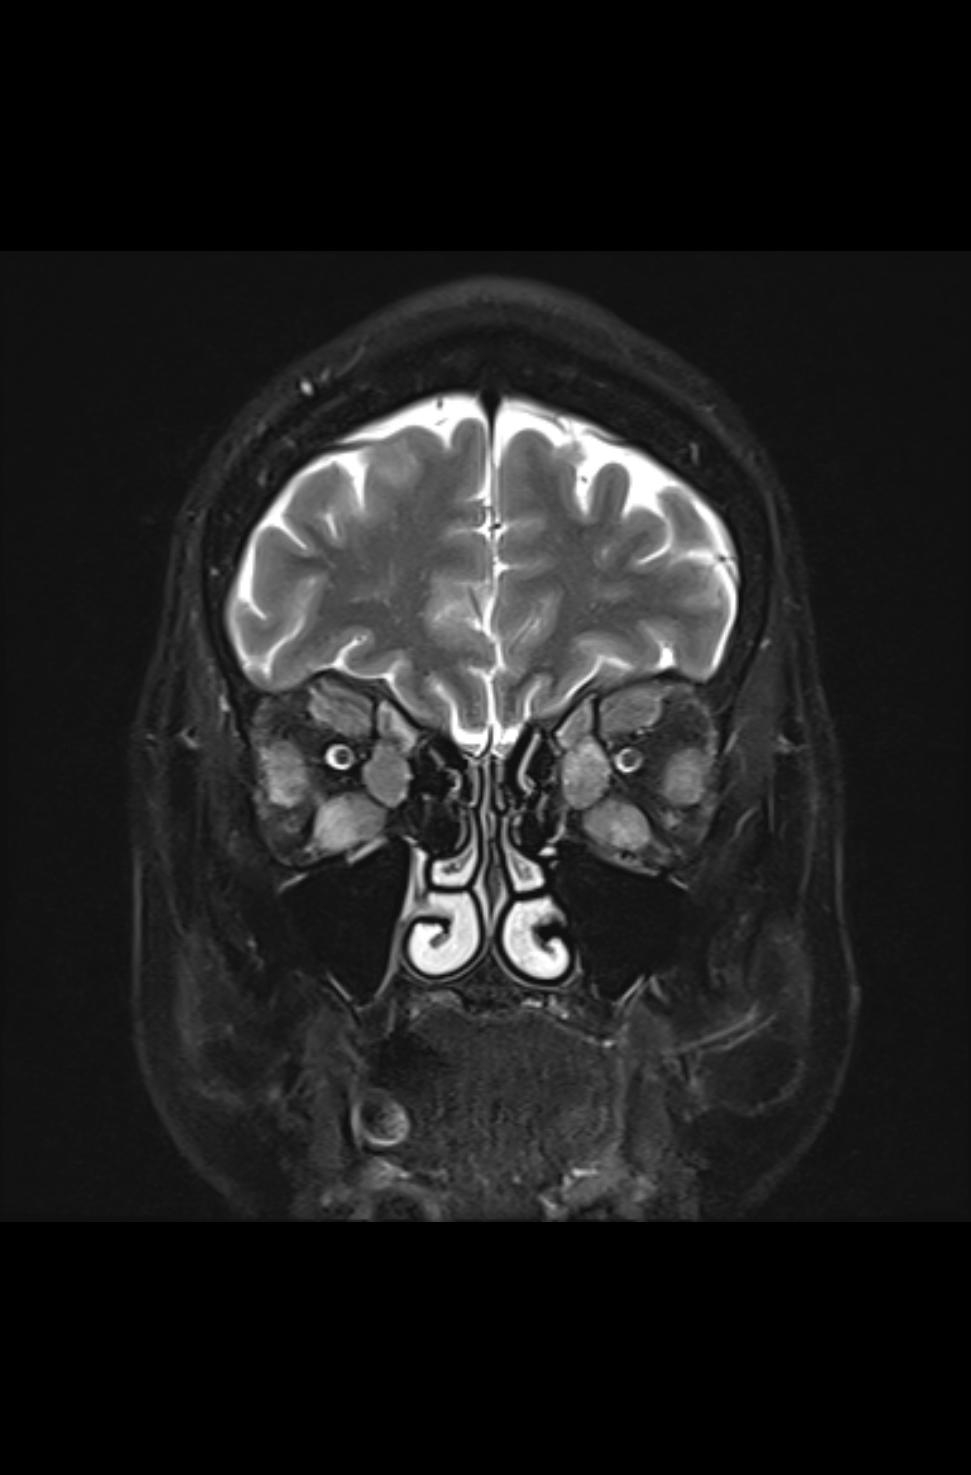

Es zeigen sich die typischen Verdickungen der Muskelbäuche der äußeren Augenmuskeln und ein Exopthalmus (Bild 3-3). In der koronaren, T2-gewichteten Sequenz mit Unterdrückung des Fettsignals (Fettsättigung) zeigt sich ein ausgeprägter Befund der endokrinen Orbitopathie mit Beteilung der Rectus-Muskeln beider Orbitae und einer Beteiligung des Musculus obliquus superior beidseits. Zusätzlich ist ein Ödem im Musculus rectus inferior beidseits, im Musculus rectus lateralis rechts, im Musculus rectus medialis links und im Musculus obliquus superior rechts abgrenzbar (Bild 3-1), welches auf eine akute entzündliche Aktivität deutet.